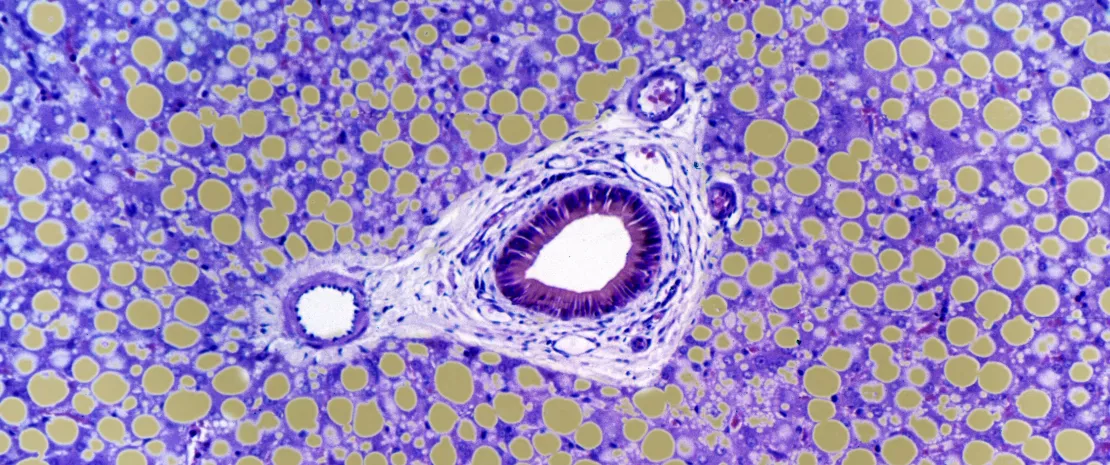

À partir d’une cohorte nord-américaine et européenne, une équipe internationale a étudié le mycobiote intestinal de 59 patients atteints d’hépatite alcoolique, 15 patients ayant une consommation problématique d’alcool* présentant différents stades d’atteinte hépatique, et 11 sujets contrôles. Une nette prolifération de Candida a été observée dans les deux groupes de malades ainsi qu’une moindre richesse et diversité fongiques par rapport aux contrôles, chez qui le genre Penicillium dominait. Par ailleurs, une corrélation entre mycobiote intestinal et paramètres cliniques a été établie : la présence des Candida était associée à une augmentation de la fibrose péricellulaire, tandis que les Penicillium étaient liés à une inflammation moins importante et une réduction des corps de Mallory**.